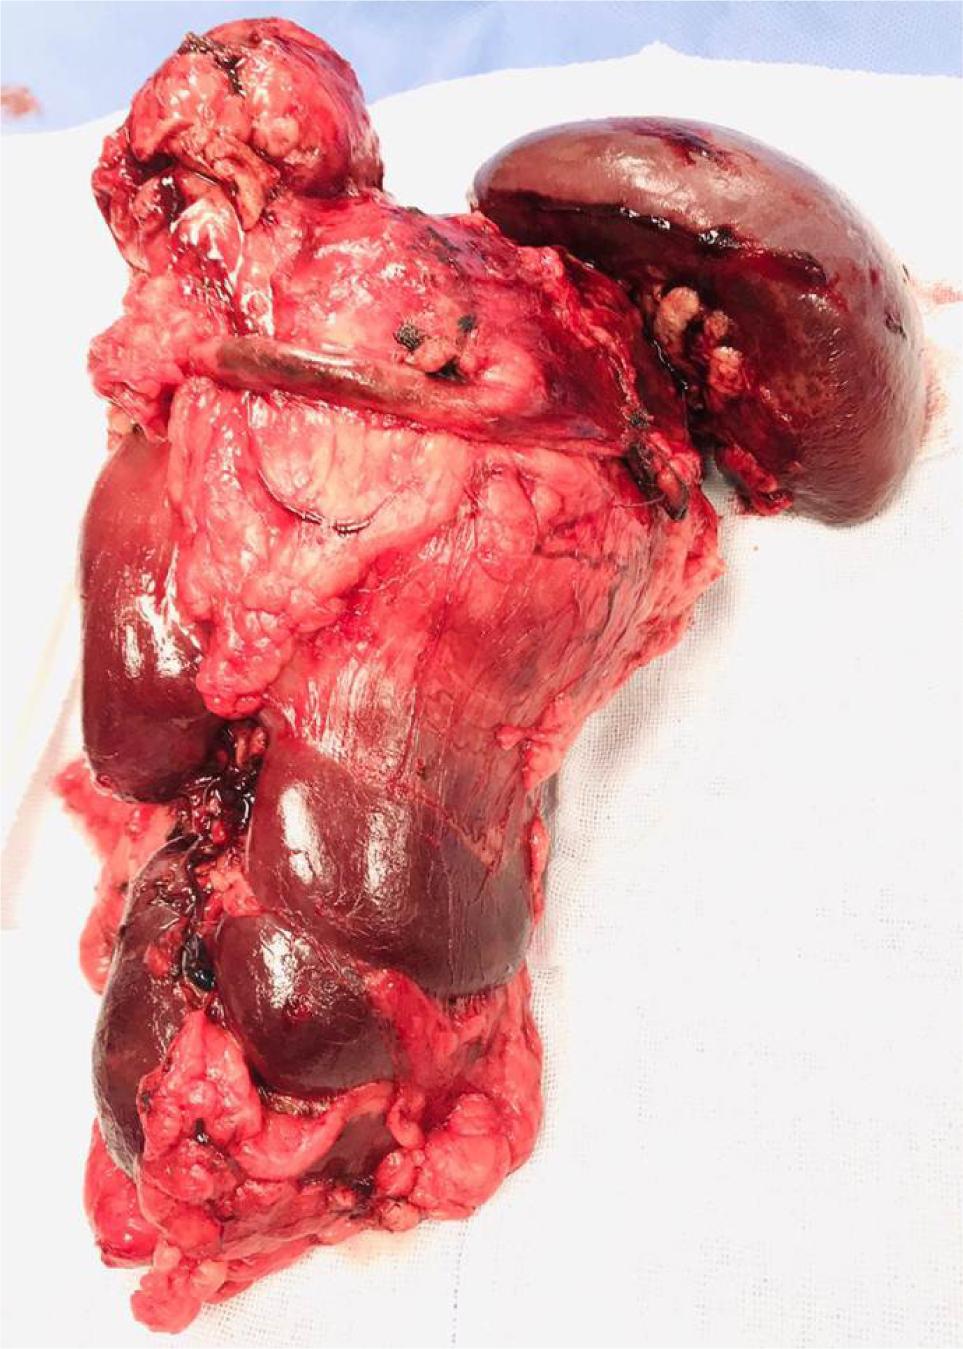

A 50-year-old man presented with left loin pain. An ultrasound, followed by a CT scan, revealed a 17.5 cm left renal mass invading the left suprarenal gland, spleen, pancreatic tail, and a part of the diaphragm. He had excellent performance status and no distant metastases. Radical nephrectomy through chevron incision under epidural block with general anesthesia was performed. Over a 2-hour operation, the entire mass was removed including the kidney, adrenal gland, spleen, pancreatic tail, and diaphragmatic fibers. There was a large chain of para-aortic lymph nodes that was removed as well. The estimated blood loss was 300 mL, and no blood transfusions were required. Chest tube was inserted and removed after 48 h. Histological examination revealed Grade 4 clear cell RCC with extension into the spleen, pancreatic tail, and diaphragmatic fibers. Invasion of main renal vein and pelvicalyceal system was identified. There was neither sarcomatoid differentiation nor lymphovascular invasion. All surgical margins were negative. The resected lymph nodes were reactive with no evidence for cancer (Stage T4N0). Preoperatively, Hgb was 12 g/dL and eGFR was 85 mmol/L. On the first postoperative day, Hgb was 10 g/dL and eGFR dropped to 60 mmol/L, and these values were nearly stable during hospital admission. Four weeks post operation, the patient was reviewed. His wound had healed well, with no complications. Chest X-ray was normal. Hgb did rise to 13 g/dL, and eGFR was 80 mmol/L. The patient was discharged after a 3-day uneventful hospital stay. Six months’ CT scan did not show any evidence for cancer recurrence. We referred the patient to medical oncology team, and we agreed on surveillance, and systemic therapy was not offered. Within that short term follow-up, the patient recovered well and did not show evidence for residual or recurrent cancer. Patient’s consent was obtained for data collection and publication. Ethical approval was not required. Figure 1 is a CT section showing the advanced renal mass and Figure 2 is an operative image for the resected kidney, spleen and pancreatic tail.

Figure 1: Axial CT abdomen showing large left renal mass infiltrating the spleen and pancreas.